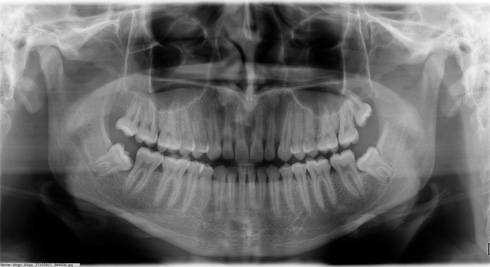

Também chamada de ortopantomográfica. Permite em uma única tomada, a visualização das estruturas do complexo maxilo-facial , conferindo portanto sua utilidade em todas as especialidades. Devido ao posicionamento do paciente (afastado do filme) a imagem não possui a mesma riqueza de detalhes finos como na periapical, porém vantagens como ampla cobertura da área examinada, a projeção das estruturas anatômicas com reduzida superposição , além da baixa dose de radiação, são justificativa de sua crescente aceitação.

Exame composto de uma tomada radiográfica panorâmica, periapicais boca toda e interproximais de molares e pré-molares. Alia a amplitude de visualização da panorâmica associada com a riqueza de detalhes obtidas nas radiografias periapicais e interproximais que somada a um exame clínico minucioso permite um diagnóstico clínico mais preciso.